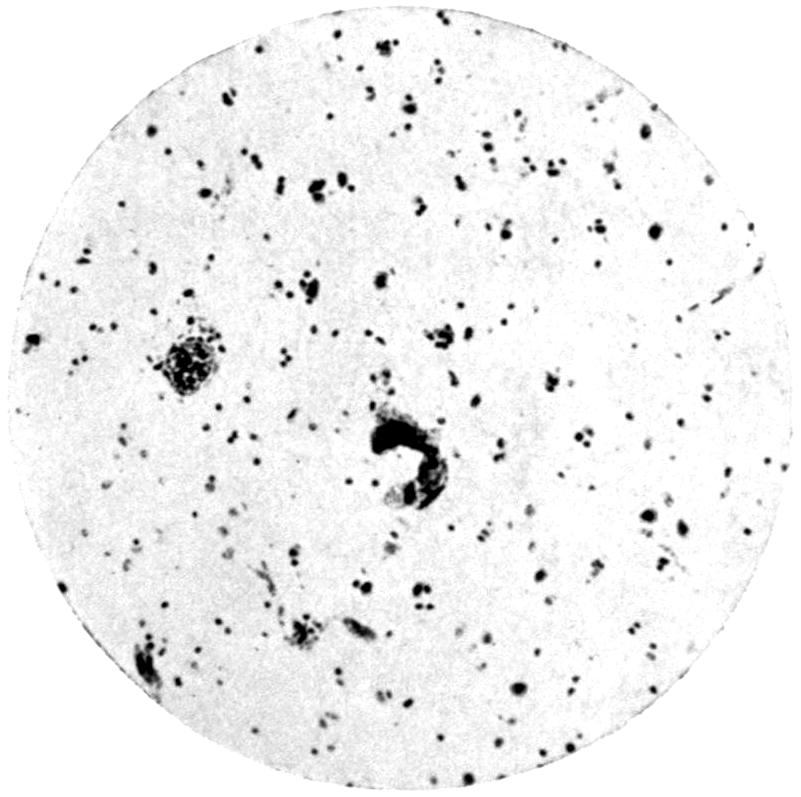

Plate III. 95